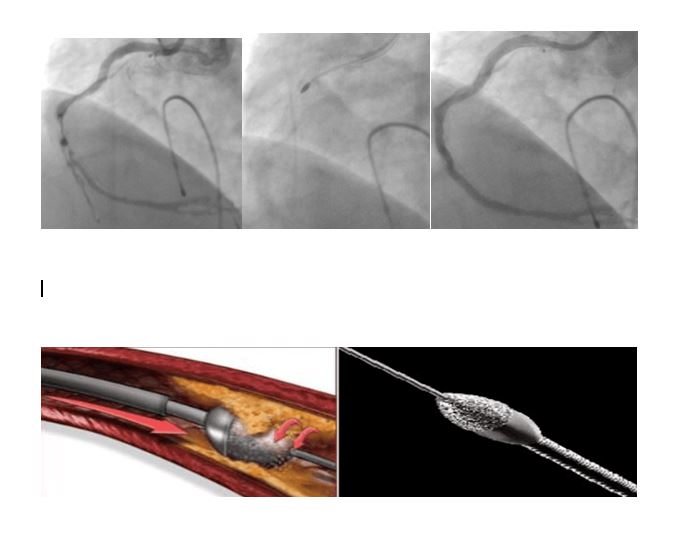

“Kalp damar hastalığı, koroner arter denilen, kalbi besleyen damarların tıkanması sebebiyle olmaktadır. Bu tıkanmaların en sık görülen sebebi ise ateroskleroz olarak adlandırılan damar duvarında yağlı plakların birikip zaman içerisinde damar boşluğuna doğru ilerleyip damar içinde kan akışını engellemesidir. Yağlı plaklar bazen kireçlenerek daha katı ve sert plaklar oluşturmaktadır. Bu kireçlenmiş plaklar ise bazen tıkanıklığı açmakta kullanılan balon/stent gibi malzemelerin geçişini engellemekte ve imkânsız kılmaktadır. Sonuçta balon/stent damar tıkanıklığı içerisinden geçemediği için tıkanıklık açılamamaktadır. Ek olarak, uygun olmayan malzemelerin kullanılması ile damarda yırtılma ve delinme gibi sorunlara yol açarak hastanın hayatını tehlikeye atan durumlar ortaya çıkmaktadır.Bu sert plakların açılmasında birtakım yeni teknolojiler kullanıma girmiştir. Bunlardan biri rotablatör (tıraşlama cihazı)’dür. Tıraşlama yöntemi ile damarı tıkayan kireçli plak yapısı parçalanarak darlıklar açılmakta, arkasından da balon/stent işlemi yapılmaktadır. Bu teknolojinin bir diğer faydası ise sert plaklara uygulanan stentin ileride tıkanma ihtimalini azaltmasıdır. Hastamızın sırasıyla; işlem öncesi, işlem esnasında ve işlem sonrasına ait sağ kalp damarına ait görüntüler izlenmektedir. Biz de merkezimizde ilk defa uyguladığımız bu işlemi başarı ile gerçekleştirdik ve hastamızı sağlığına kavuşturduk.”